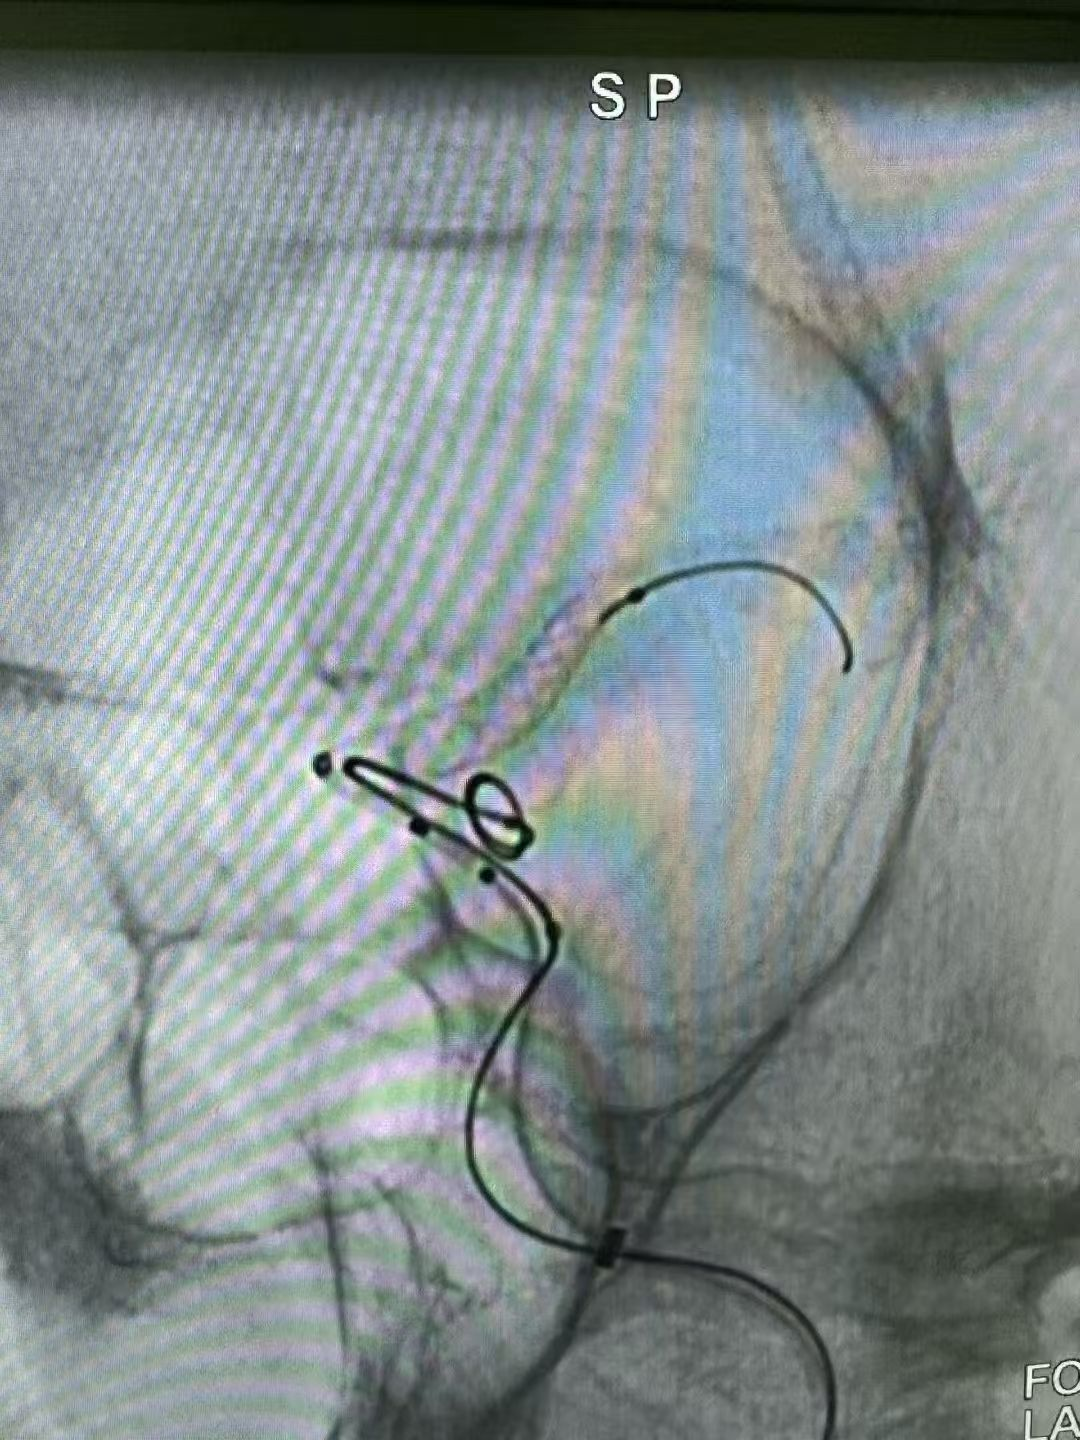

近日,桂平市中医医院脑病科介入团队成功为一例复杂颅内动脉瘤患者实施了微创介入手术。该手术采用了“弹簧圈联合血流导向密网装置”的先进技术,为患者解除了颅内“不定时炸弹”的威胁。此类高难度手术的成功开展,标志着我院在脑血管疾病的微创介入治疗领域具备了处理复杂病例的能力。 警惕隐匿的“脑内危机”:认识颅内动脉瘤 颅内动脉瘤并非肿瘤,而是颅内血管壁因局部薄弱而异常膨出的一个“小血泡”,其最大风险在于破裂出血。一旦破裂,致死致残率极高。临床上,动脉瘤在破裂前有时会因压迫邻近的神经而出现预警信号,如突发剧烈头痛、眼睑下垂、视物模糊等。 本例患者因“突发头痛伴左侧眼睑下垂”来院。经急诊脑血管造影(DSA)检查,确诊为左侧颈内动脉后交通段动脉瘤。该动脉瘤形态不规则、瘤颈宽大,治疗难度较高。若采用传统单一技术,可能面临诸多挑战。 微创介入:“双管齐下”的精准治疗策略 经过严谨的术前讨论评估,脑病科周辉主任团队为患者制定了“弹簧圈联合血流导向密网装置”的个体化手术方案。 与传统的开颅手术相比,该微创介入技术仅需通过大腿根部股动脉进行穿刺,利用一根极其精细的微导管,在数字减影血管造影机(DSA)的实时引导下,将装置精准输送至病变血管。手术团队首先将弹簧圈填入动脉瘤囊内,促进内部血栓形成;随后,将一张血流导向密网装置释放并覆盖于瘤颈开口处。该装置能有效引导血流主流远离动脉瘤,从而为动脉瘤的自然萎缩闭合创造条-件,显著降低远期复发风险。 在麻醉科、介入导管室的通力协作下,手术顺利完成。术后造影显示,动脉瘤栓塞效果满意,载瘤动脉通畅。患者术后恢复良好,次日即可下床活动,头痛症状缓解,神经功能得到改善。 学科进展:为复杂脑血管病患者提供更多选择 脑病科周辉主任介绍,“弹簧圈联合血流导向密网装置”技术是目前处理大型、巨大型、宽颈等复杂颅内动脉瘤的先进方案之一。这一技术的应用,拓展了微创介入治疗的适应范围,使得一些以往难以通过微创方式治疗或需行高风险开颅手术的患者有了新的选择。 健康提示:早筛早诊是关键 颅内动脉瘤多为隐匿发生。建议有高血压、高血脂、长期吸烟、有脑血管病家族史等高危人群,应重视脑血管健康筛查,做到早发现、早诊断、早治疗。切勿忽视突发性剧烈头痛、眼睑下垂等身体发出的“预警信号”。 桂平市中医医院脑病科始终致力于追踪和应用前沿技术,以专业的医疗团队和丰富的临床经验,为百姓的脑血管健康保驾护航。 健康咨询 健康咨询电话 0775—3384702 0775—3372569 门诊地址 桂平市中医医院 2号楼3楼366诊室 住院地址 桂平市中医医院 1号楼7楼、2号楼7楼 |